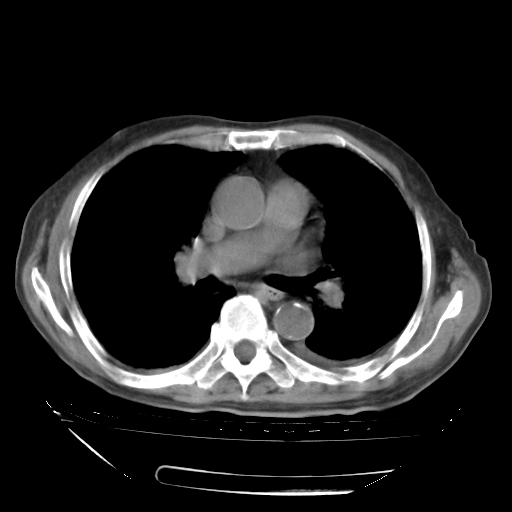

甲强龙80mg/日+抗结核治疗(异烟肼+利福霉素+乙胺丁醇)10天。复查肺部CT。

治疗10天肺部CT